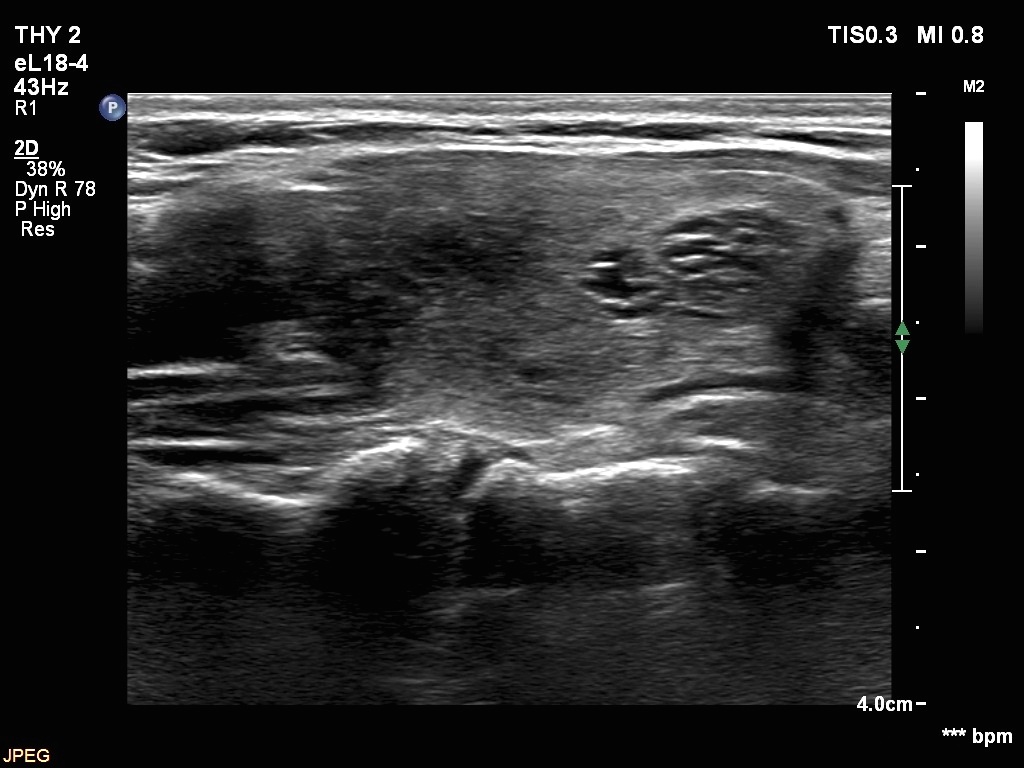

Left lobe, another longitudinal view. The lobe had indeed two spongiform cystic nodules.